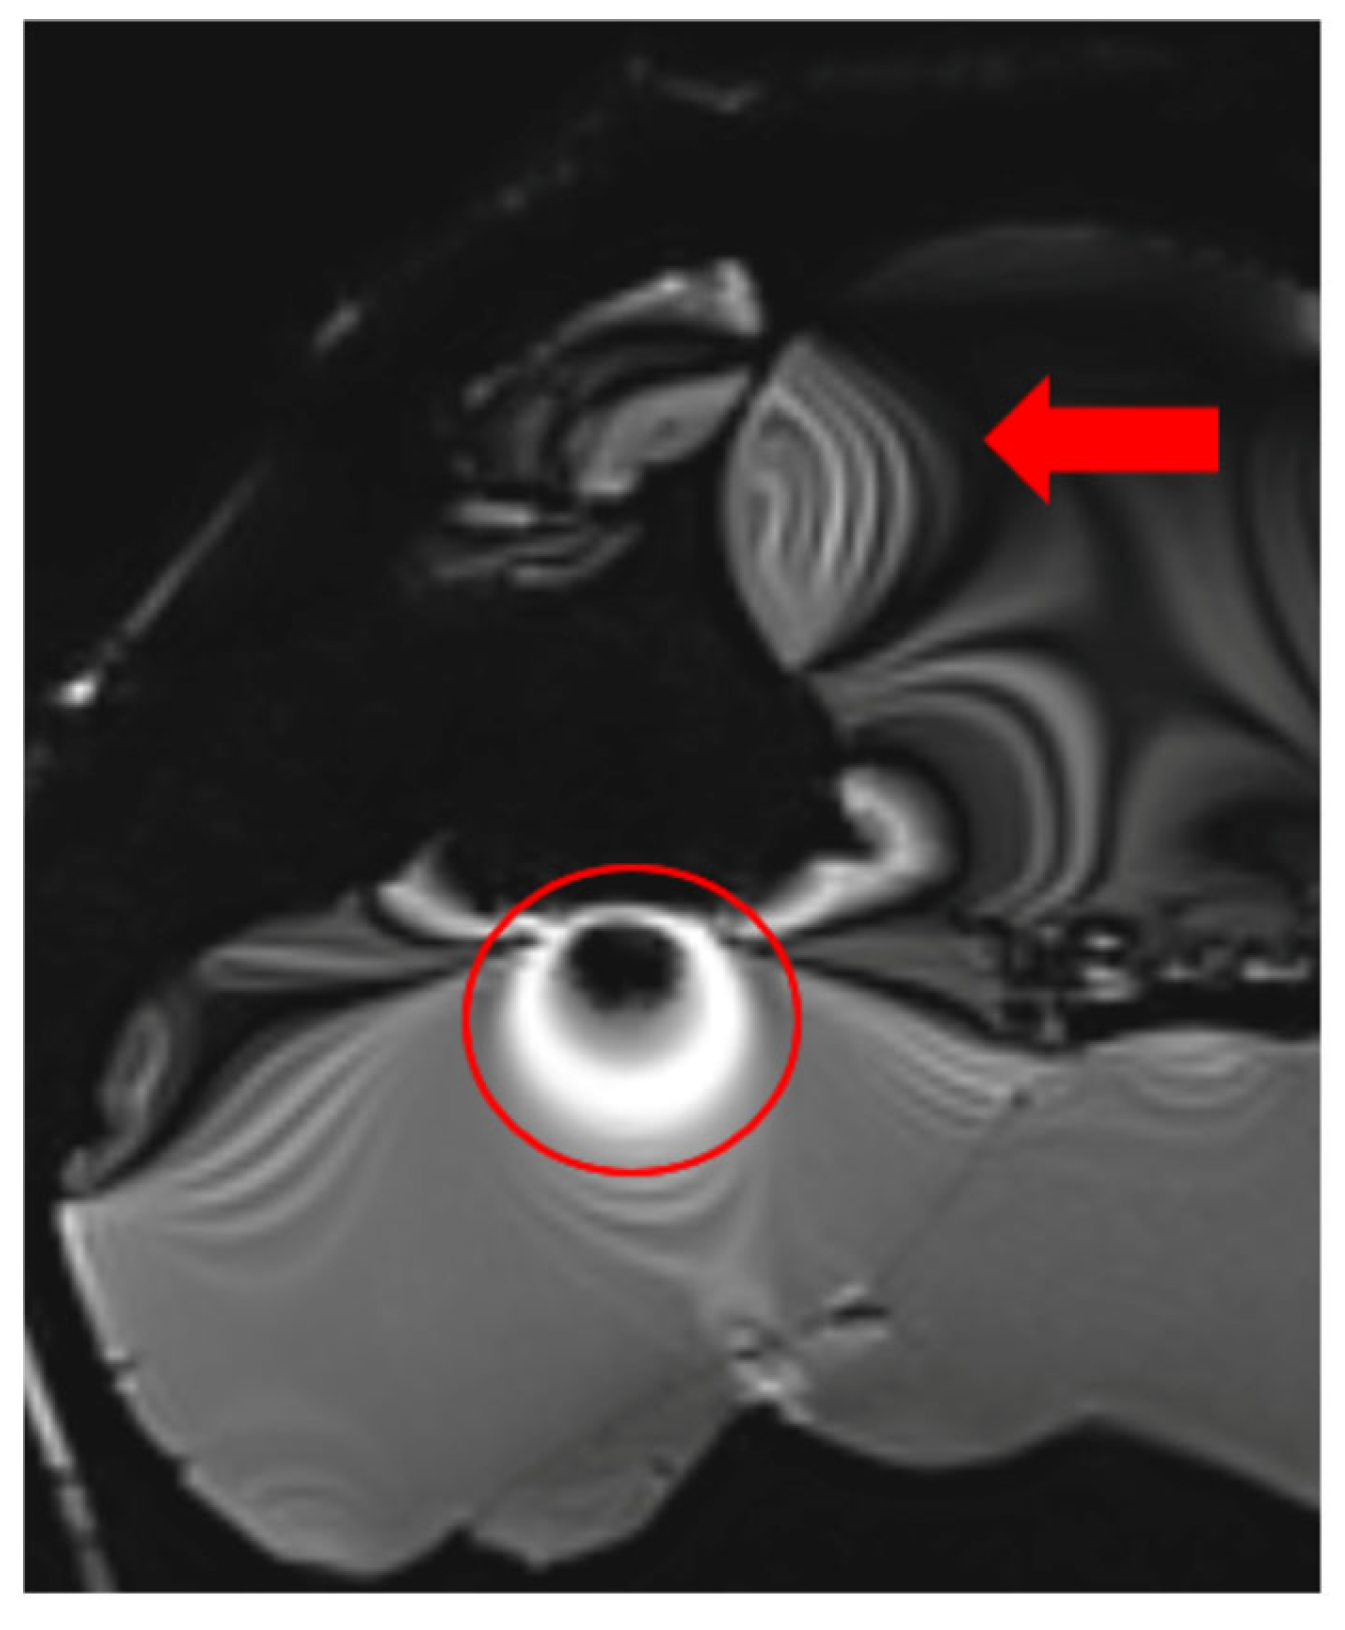

The extent of MRI signal dropout is also influenced by the echo time (TE); a longer TE exacerbates artifact formation at the interface of soft tissues, bone, and air. This effect is evident in images (Figure 3) obtained using t1_starvibe_tra, t1_vibe_fs_tra, and t2_tse_fs_tra.

Figure 3.

Images illustrating the effect of prolonged echo time (TE) on artifact formation at the interfaces of soft tissue, bone, and air (a) t1_starvibe_tra sequence showing signal dropout and distortion near the simulated tumor region, highlighted by the red circle, (b) t1_vibe_fs_tra sequence, with the red arrow indicating residual artifact intensity in the vicinity of the implant interface, and (c) t2_tse_fs_tra sequence, where the red circle marks susceptibility-induced signal loss at the tumor location.